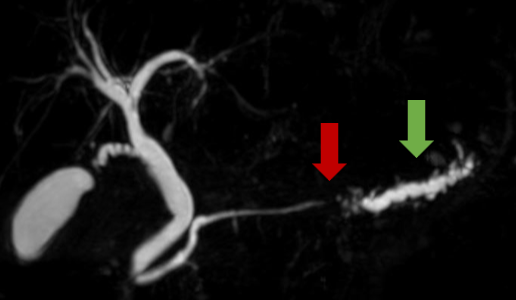

【膵腫瘍の症例】膵管が病変部で狭くなり、流れが悪くなった上流側の膵管はふくらんでいます。